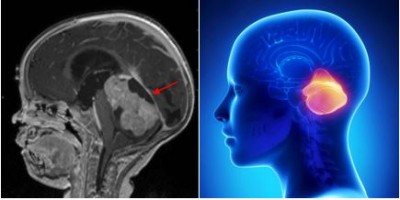

Khối u não: Tổng quan và các khái niệm cơ bản

Khối u não hình thành do sự phát triển bất thường của các tế bào trong não. Tốc độ phát triển và vị trí của khối u não sẽ quyết định đến chức năng thần kinh của bệnh...

Khối u não ở người lớn

U não ở người lớn là các khối u não xuất phát từ những nhóm tế bào nằm ngoài kiểm soát của có thể. U não được gọi là khối u nguyên phát nếu chúng bắt...